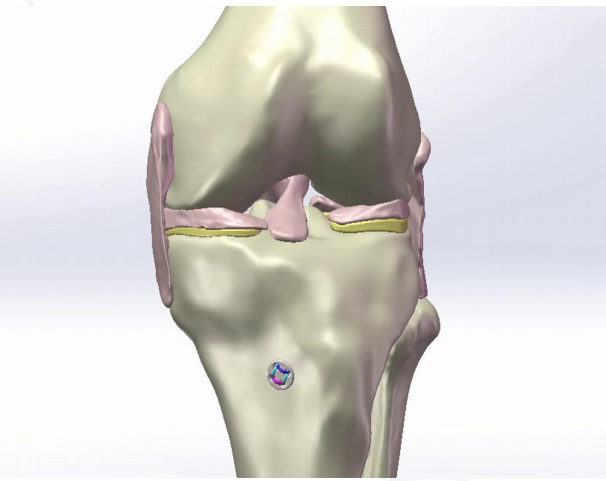

3D Model Demonstration

分型与术式选择

分型及术式

Ⅰ型:撕脱骨折块 BC≤15mm;AE/AD <1/2

术式:高强线“双环扣”+单袢

手术技术:高强度缝线双环钛扣技术